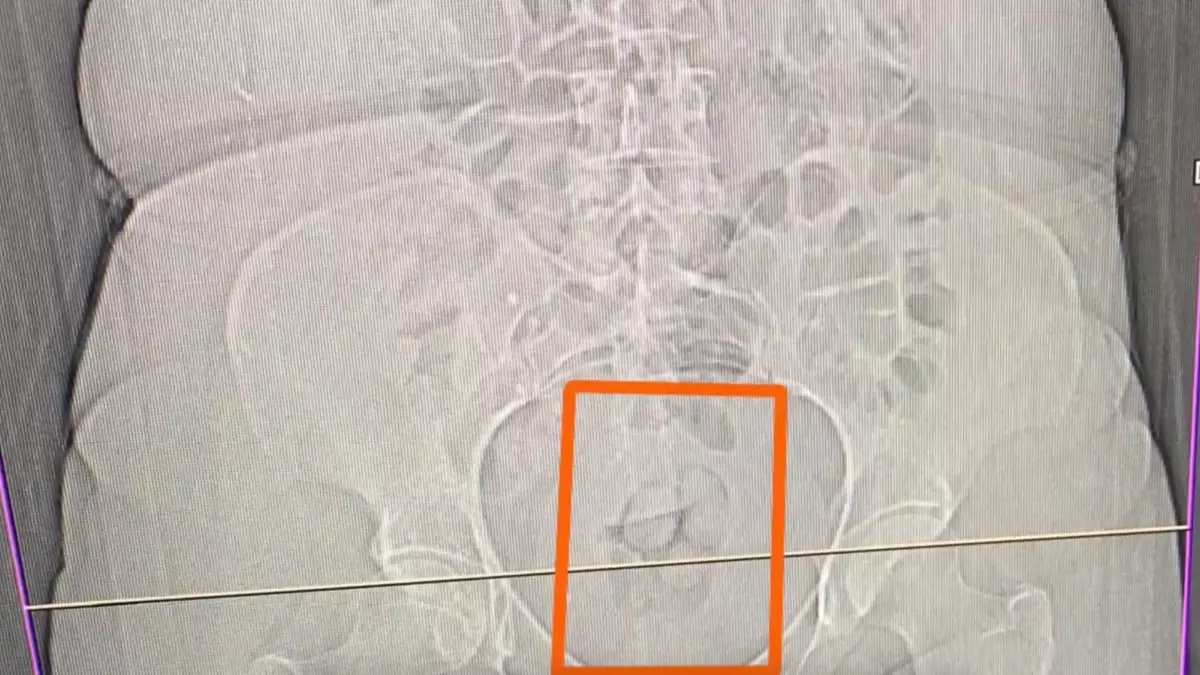

İl Emniyet Müdürlüğü Narkotik Suçlarla Mücadele Şube Müdürlüğü ve İstihbarat Şube Müdürlüğü ekipleri, uyuşturucu madde ticareti yapan ve kullanan şüphelilere yönelik çalışma yaptı. Bu kapsamda F.U.C., R.B.C., Ö.K. ve S.S. isimli kişilerin Erzincan'a uyuşturucu madde getirileceği bilgisine ulaşıldı. Şüphelilerin içerisinde bulunduğu araç, takibe alınıp durduruldu. Araçta yapılan aramada 16,40 gram metamfetamin geçirildi. Gözaltına alınan 4 şüpheliden S.S.'nin şüpheli davranışları üzerine tomografi çekildi ve midesinde 21,39 gram metamfetamin olduğu tespit edildi. Uyuşturucu madde doğal yollarla çıkartılırken, adliyeye sevk edilen 4 şüpheli hakkında 'Uyuşturucu veya uyarıcı madde imal ve ticareti" suçundan işlem yapıldı.